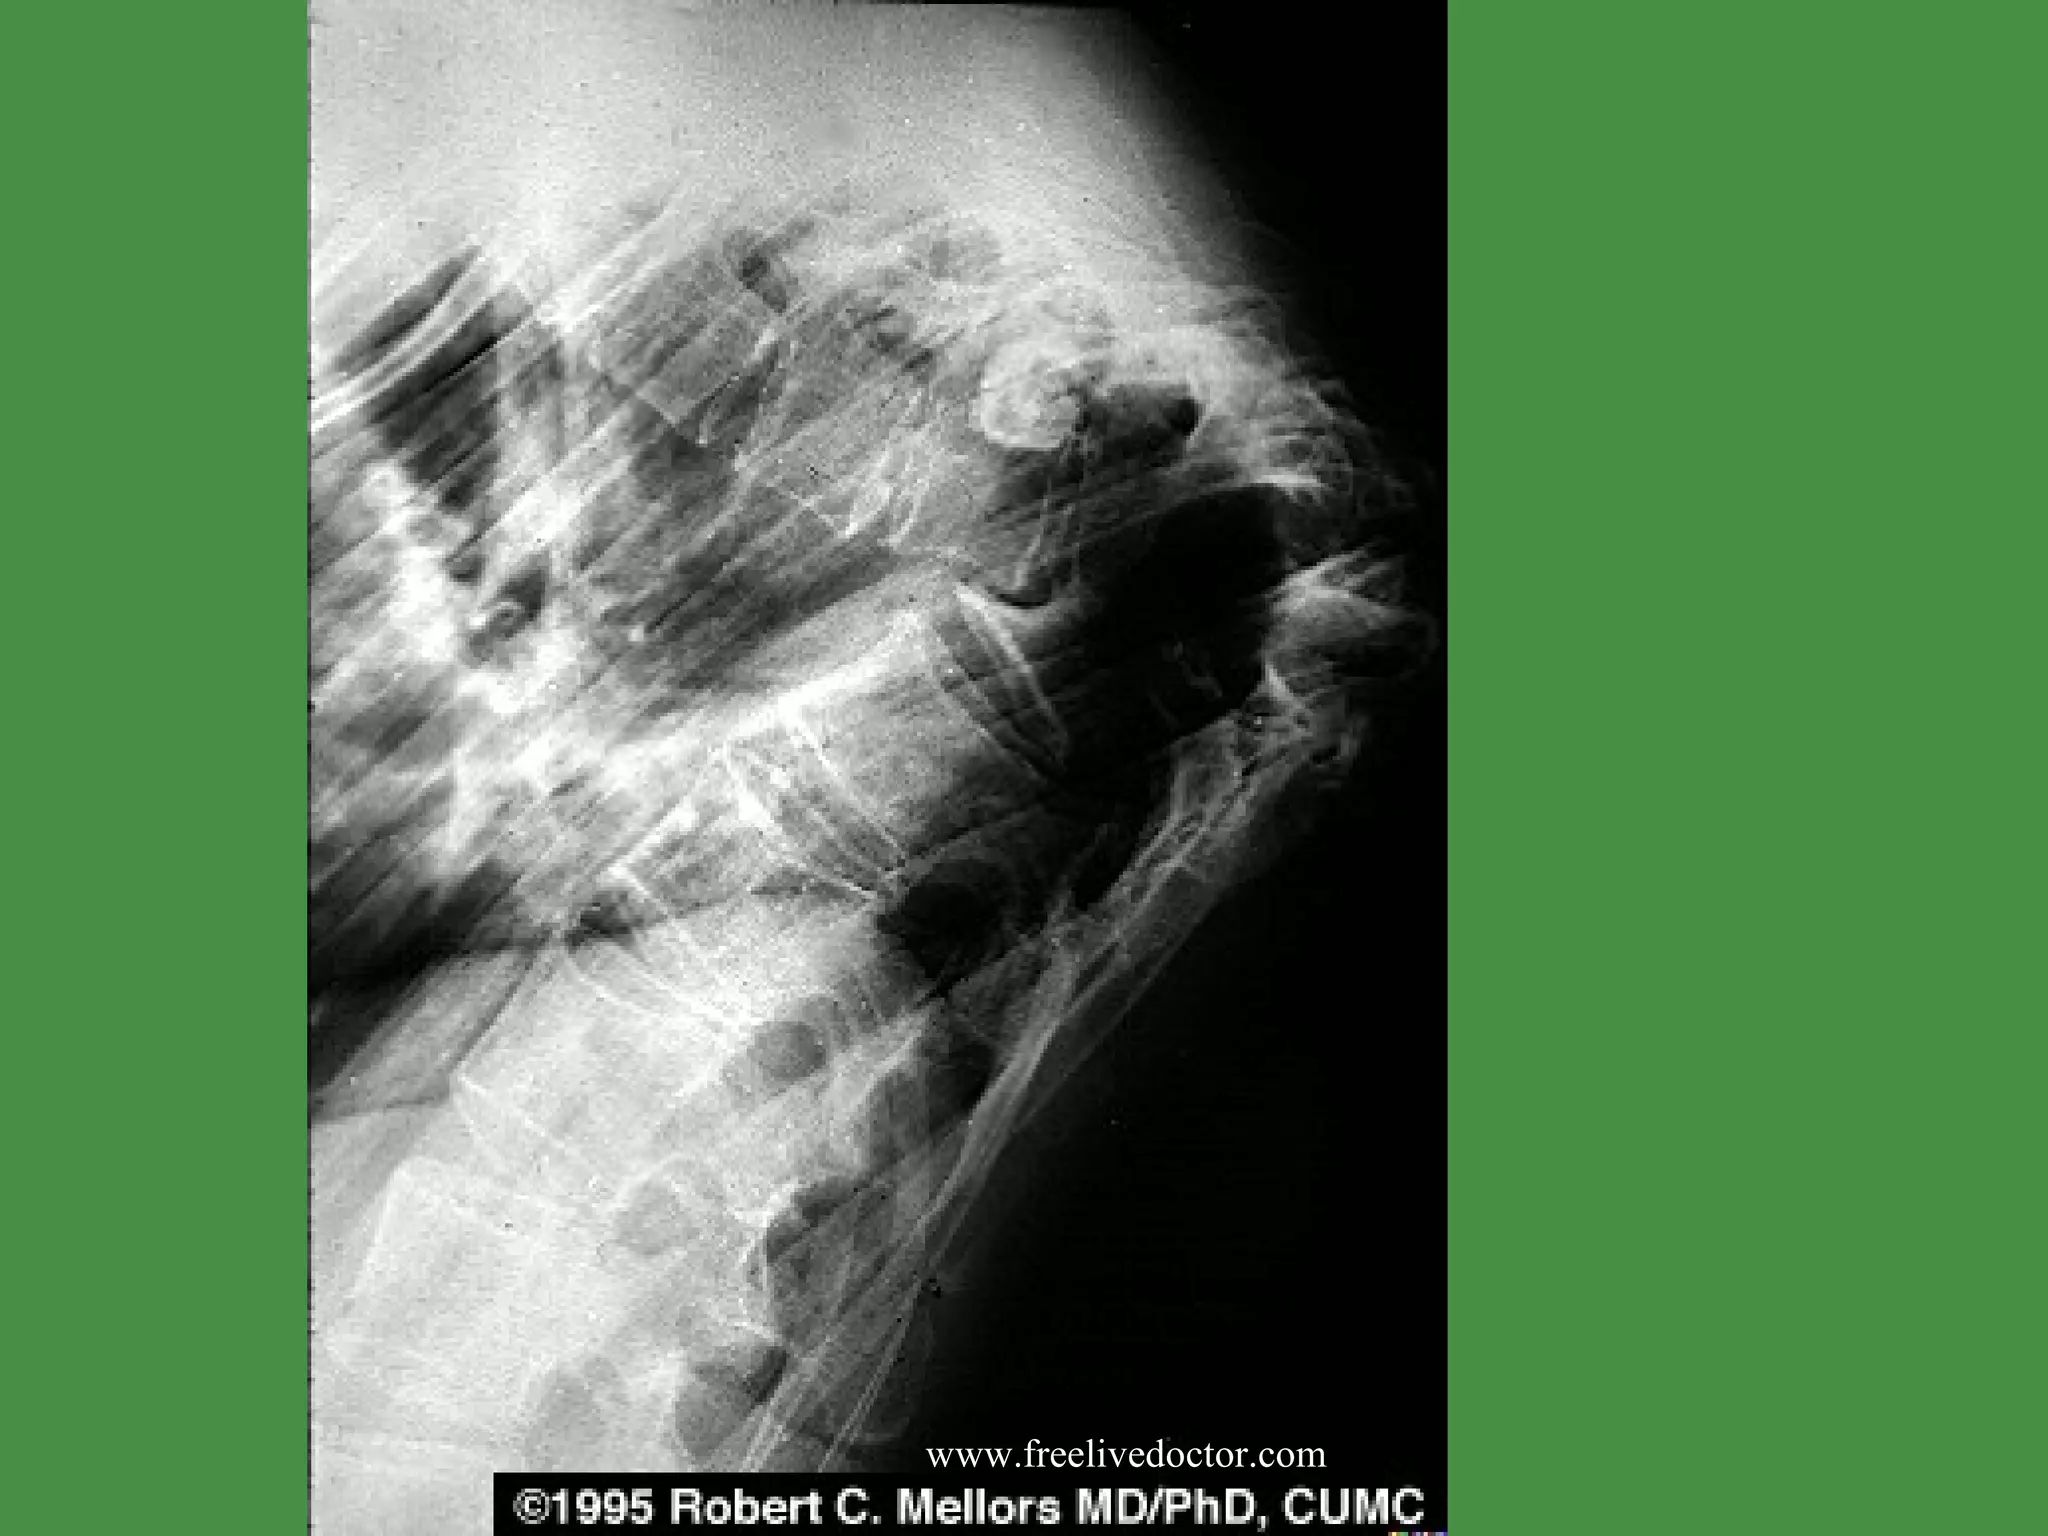

O STEOPOROSIS(cont.) Loss of height ,  kyphos coliosis, lordosis X-rays: generalized radiolucency of bone (  osteopenia ) Dual Energy X Ray Absorptiometry  ( DEXA.) NORMAL SERUM CALCIUM,PHOSPHORUS,and ALKALINE PHOSPHATASE. Micro:  t hinned cortical and trabecular bone  Treatment :  e strogen replacement therapy ,  w eight bearing exercise,Calcium and Vitamin D ,  Biphosphonate ( Alendro  nate)  ,  Calcitonin.  www.freelivedoctor.com

T B  O STEOMYELITIS(cont.) Pain or tenderness, fever, night sweats, weight loss. Caseating granulomas with extensive destruction of the bones. Common site : Thora c ic and lumbar vertebrae ( Pott ´s  Disease)  www.freelivedoctor.com

T B  O STEOMYELITIS(cont.) Complications. Vertebral compression fracture Psoas abscesses Amyloidosis www.freelivedoctor.com